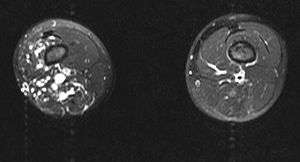

MRI